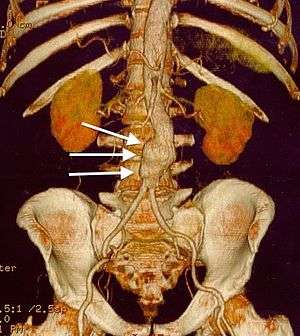

CT reconstruction image of an abdominal aortic aneurysm (white arrows) | |